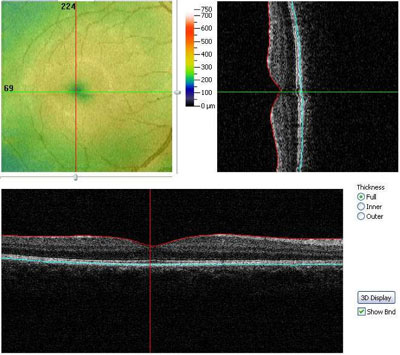

Die Schichten der Netzhaut sind als ebenmäßige Linien zu erkennen. Im Zentrum, der Stelle des schärfsten

Sehens ( Fovea), ist die Netzhaut am dünnsten. (Man sieht hier eine leichte "Einbuchtung".)

Die zentrale "Einbuchtung" ist verloren gegangen. Die Netzhaut zeigt sich abhängig von der Erkrankung verdickt, verdünnt oder unregelmäßig verändert. Einlagerungen/Ablagerungen, wie sie z.B. bei der trockenen Makuladegeneration auftreten, können genau dargestellt werden. Ein wichtiges Indiz für die (beginnende) feuchte Makuladegeneration ist eine Flüssigkeitseinlagerung oder Blutung in der Netzhaut. Auch diese Veränderungen können exakt dargestellt werden. Auch für Verlaufskontrollen, nach erfolgter Behandlung, ist es eine unverzichtbare Untersuchung.